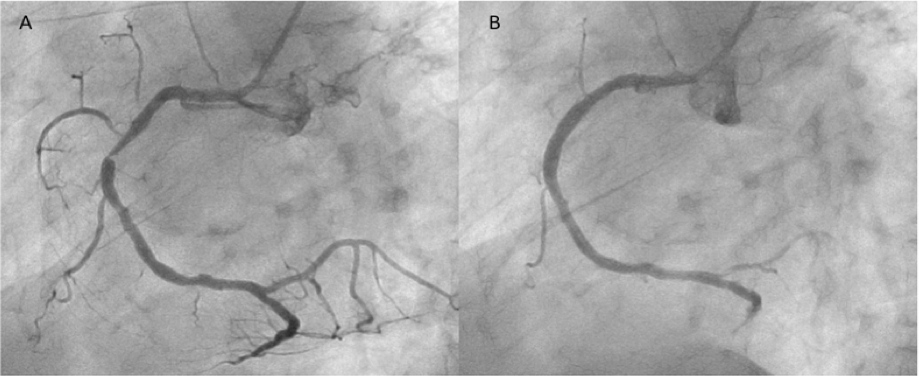

Figure 5. Angiographic images of the tortuous right coronary artery in case 2 (A) before and (B) after deployment of a 3.0 × 14 mm Nobori stent to the target lesion (click thumbnail to view larger image).

While he had been symptom free for 13 months, ISR at the target lesion was diagnosed by follow-up right coronary angiography (Figure 5A). The lesion was subsequently treated with a 3.0 × 14 mm Nobori stent with adjunctive postdilatation up to 16 atm using a 3.5 × 8 mm non-compliant balloon, and he was discharged with an excellent result (Figure 5B).

Figure 6. (A) Focal in-stent restenosis of the Nobori stent site and (B) angiogram after deployment of a 3.0 × 12 mm PROMUS Element stent (click thumbnail to view larger image).

Nine months after the Nobori stent implantation, the patient was admitted for chest pain on effort. Right coronary angiography revealed a focal significant ISR of the Nobori stent (Figure 6A), and plain fluoroscopic images showed a gap in the strut in the middle of the Nobori stent, suggesting SF (Figure 7B). The fractured segment was treated with a 3.0 × 12 mm PROMUS Element stent (Boston Scientific). No further imaging was possible because of severe calcification and tortuosity. Post-stenting angiography revealed an excellent result (Figure 6B).